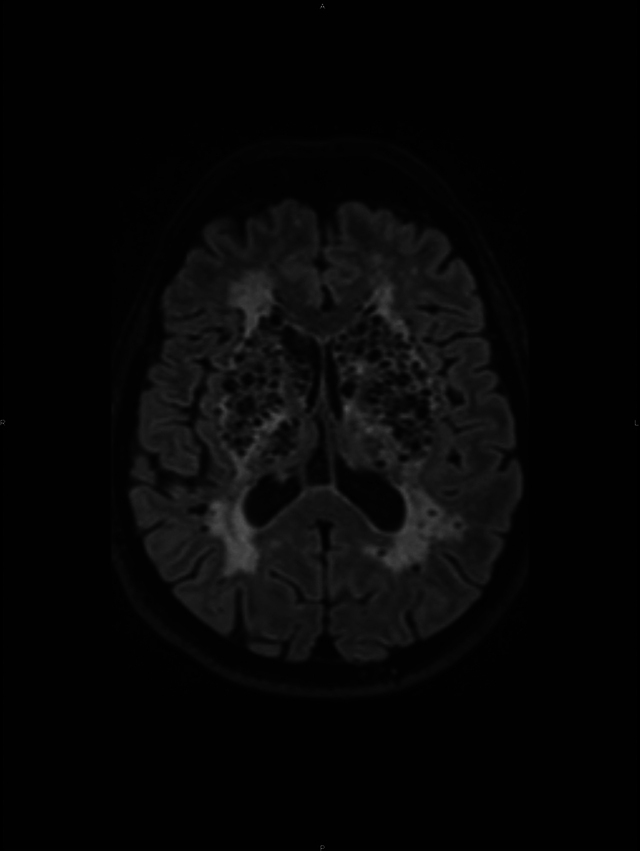

Teaching point: Perivascular spaces, also known as Virchow-Robin spaces, are fluid-filled spaces that surround the vessel walls from the subarachnoid space through the brain parenchyma.

Abstract Image